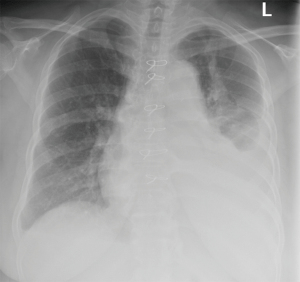

- Chest x-ray

- Pneumonia

- Asthma

- Chronic obstructive pulmonary disease

- Restrictive lung disease

- Pneumothorax

- Pulmonary embolism

- Congestive heart failure